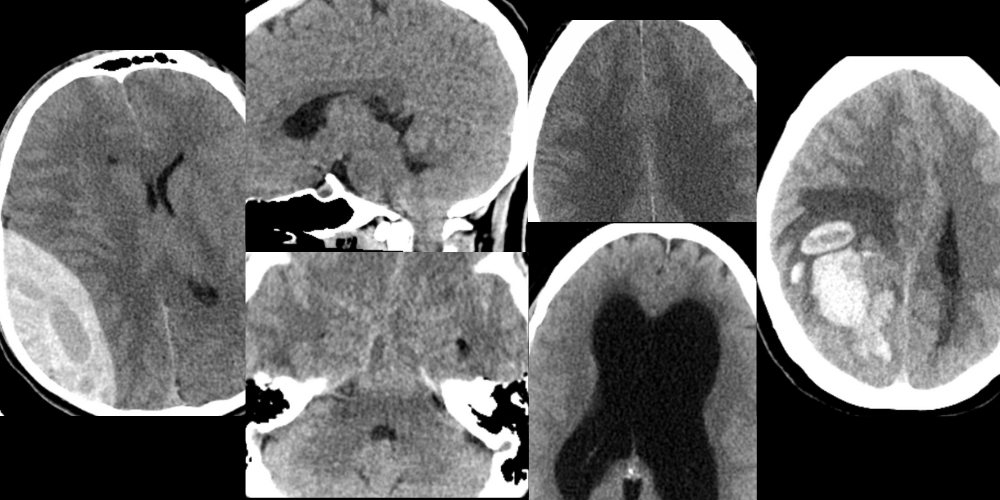

This course covers 70% of CT head interpretation knowledge needed for your shifts. Relevant to beginner & intermediate learners

• Real Cases

30+ cases, which are reviewed in scrolled format so you can test your knowledge

CT Head Basics for Clinicians - Ruling out Neurosurgical Emergencies